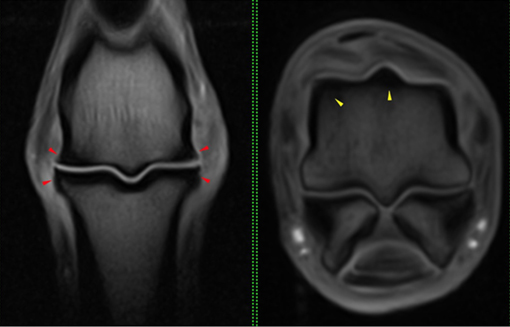

MRI:

MRI revealed degenerative joint disease of left forelimb fetlock with some subchondral bone remodelling.